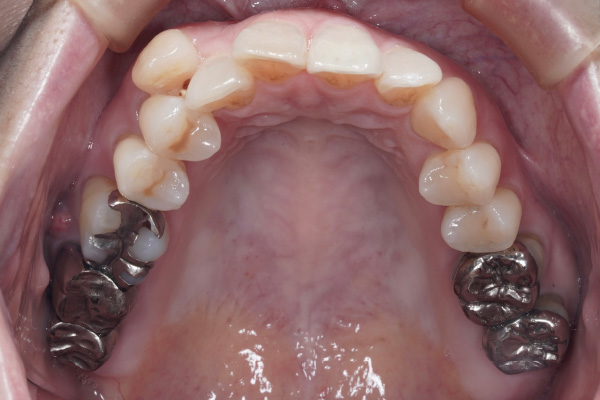

⚫︎年齢:50代

⚫︎性別:女性

⚫︎主訴:八重歯を治療したい。前歯が咬んでないのを治療したい。

⚫︎八重歯が気になる

⚫︎前歯が咬んでいない

この症例の場合も、4ヶ月→8ヶ月で目に見える変化がありました。